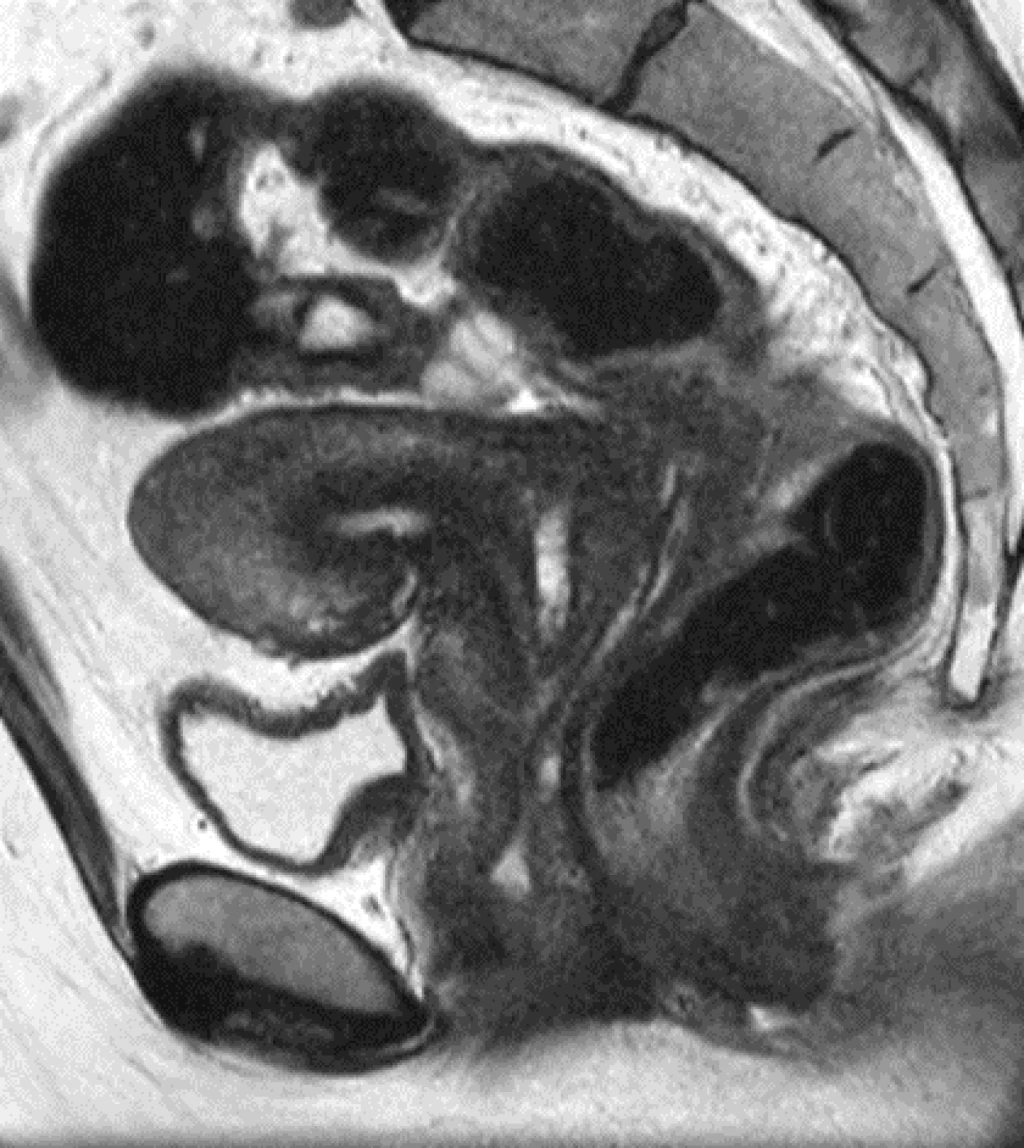

Diepe endometriose met darmbetrokkenheid

Diepe endometriose met darmbetrokkenheid bij dezelfde patiente gezien door MRI, TVE en na operatie: diepe endometriose (zie rode pijl) met musculaire infiltratie in de anterieure wand van het rectosigmoid.